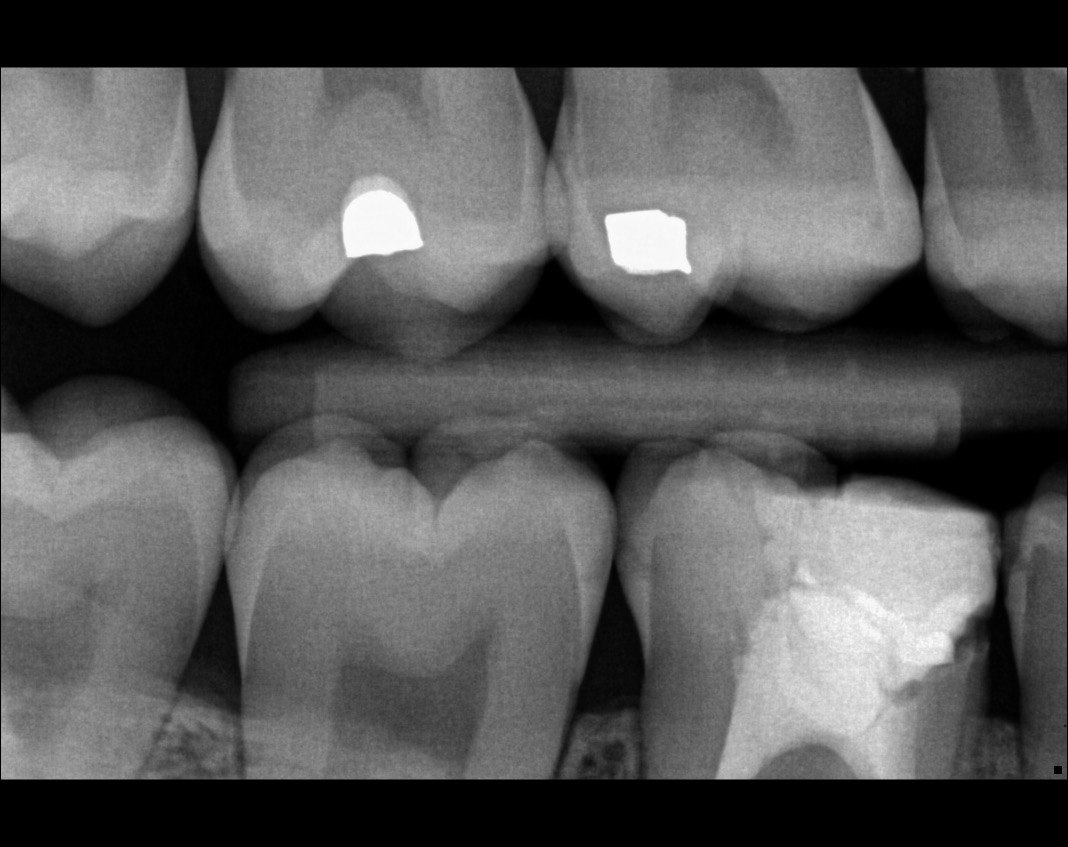

Question 26: What is the option explaining the distal surface of the tooth # 2.6 and mesial surface of the tooth # 2.7 respectively?

Question 27:  What is the option explaining the distal surface of the tooth # 2.5 and distal surface of the tooth # 2.4 respectively?

Question 28: What is the option explaining the distal surface of the tooth # 2.5?

Question 29: What is the option explaining the Mesial surface of the tooth # 2.5 and distal of tooth # 2.4 respectively?

Question 30: What option can be seen on the lower jaw of the following X ray?

Question 31: Which options can be selected for the following X ray?

Question 32: Which surface need restoration?

Question 33: What is the condition in mesial of tooth # 4.6?

Question 34: What is the level of caries on mesial of the tooth # 1.6?

Question 35: Which surface shows recurrent caries?

Question 36: What is the caries on distal surface tooth # 1.5?